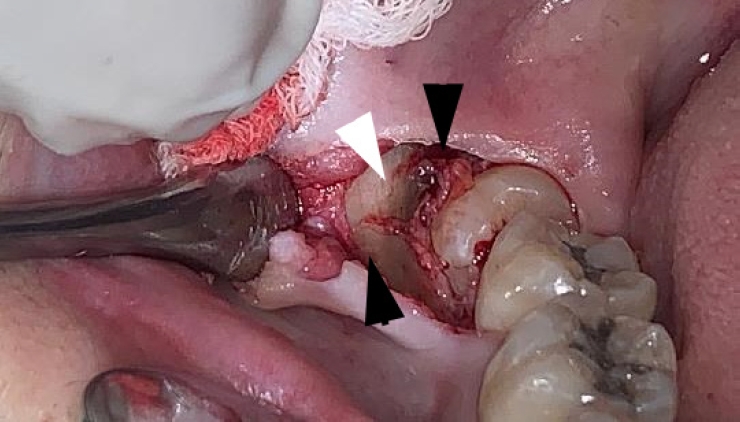

Figure 2.

Alternating bands of blue-gray and yellow discoloration of the alveolar bone observed during flap reflection for surgical extraction of the left mandibular impacted third molar.

Intraoperatively, alternating bands of blue-gray and yellow discoloration of the alveolar bone was noted around both #38 and #48. (Fig. 2 and 3) No discoloration of adjacent teeth was observed. The overlying mucosa showed no discoloration or textural changes. During alveolar bone reduction, the bone density and quality appeared normal, and no other abnormal signs or symptoms were present.